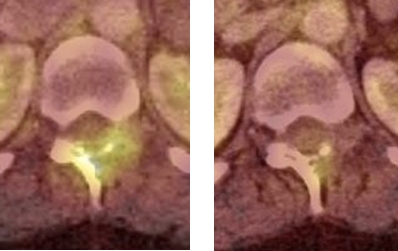

Se obtuvo un estudio PET-CT de cuerpo entero 50 minutos después de la administración IV de 7,8 mCi de 18F-FDG; el componente CT se realizó con medio de contraste yodado (equipo Siemens mCT). El estudio demostró lesiones osteolíticas hipermetabólicas en la cabeza humeral derecha, cavidad glenoidea y partes blandas adyacentes con valor de captación estandarizado (SUVmax) = 9,2. También mostró múltiples lesiones osteolíticas e hipermetabólicas vertebrales y costales con masa de partes blandas hipermetabólica que infiltra la musculatura dorso-lumbar y femoral. Se observó aumento del metabolismo en el plano cutáneo de axila izquierda y vulva, en correspondencia con lesiones ulceradas, así como también un nódulo hipofisario de 14 mm, hipermetabólico, con SUVmax = 22,5 (figs. 1,2 y 3 A). Los pulmones, mediastino, hígado, bazo, glándulas suprarrenales y páncreas no presentaron alteraciones del metabolismo ni tampoco se identificaron adenopatías hipercaptantes.

Un 18FDG PET-CT de control post-terapia (figs. 1,2 y3 B) mostró significativa disminución metabólica de la lesión hipofisaria, del componente de partes blandas en hombro derecho y de las lesiones en columna, con persistencia sin cambios de las lesiones osteolíticas en TAC. Dada la respuesta parcial a la terapia, se inicia segundo curso de vinblastina semanal 6 mg/m2 por 6 semanas y prednisona 40 mg/m2 por 3 días a la semana.